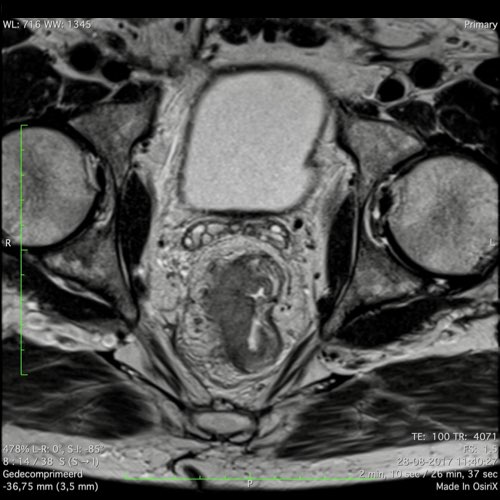

Hình ảnh

Các hình ảnh được cung cấp cho thấy ung thư biểu mô tế bào nhẫn với tình trạng dày lan tỏa thành trực tràng, hình ảnh bia bắn điển hình, và sự xâm lấn mỡ mạc treo trực tràng.